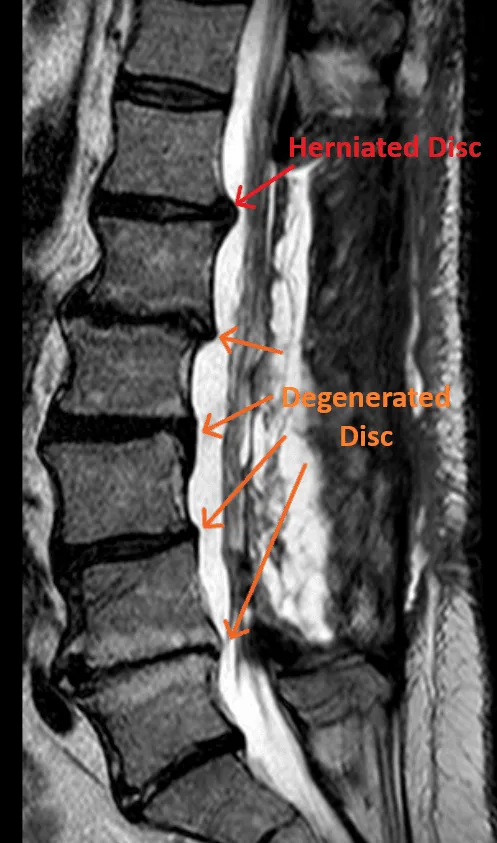

MRI of the spine highlighting herniated and degenerated discs.

Doesn't Treat Actual Pain Source